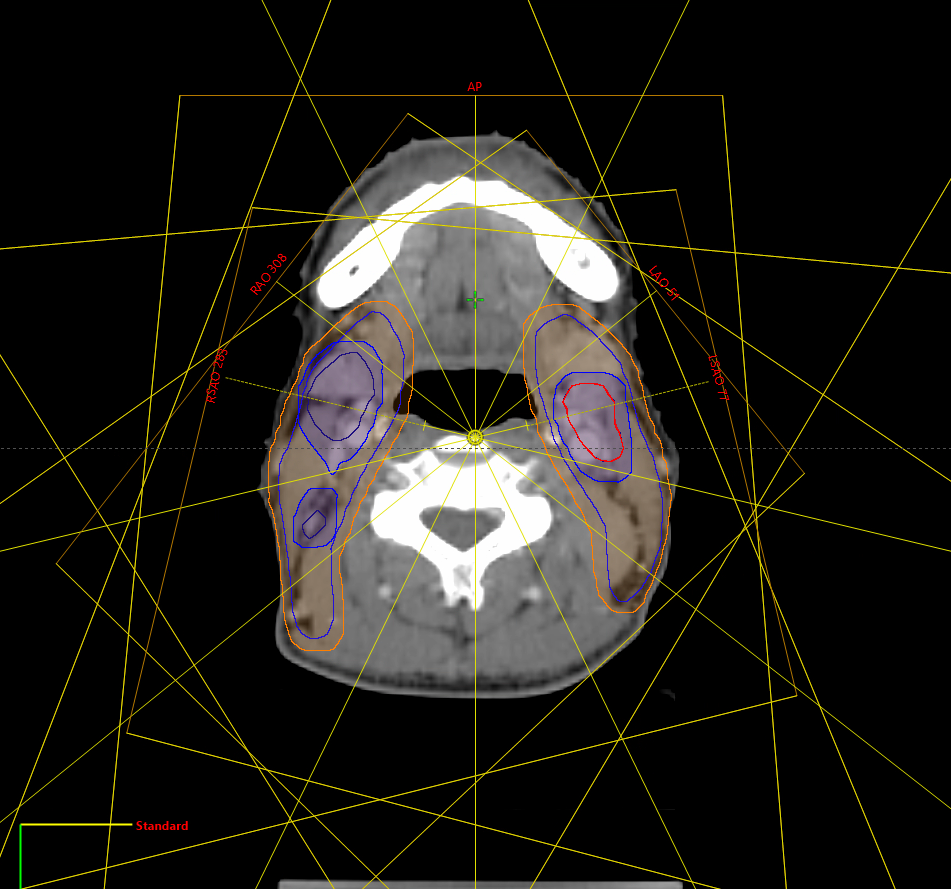

Our Intensity-Modulated Radiation Therapy (IMRT) plans are designed to deliver precise radiation doses to the tumor while minimizing dose to surrounding normal tissues. We utilize advanced optimization algorithms to create highly conformal dose distributions, ensuring optimal target coverage and organ sparing.

Volumetric Modulated Arc Therapy (VMAT) offers faster delivery times and superior dose conformity. Our team is expert in VMAT planning, balancing modulation and delivery efficiency to provide the best possible treatment for your patients.